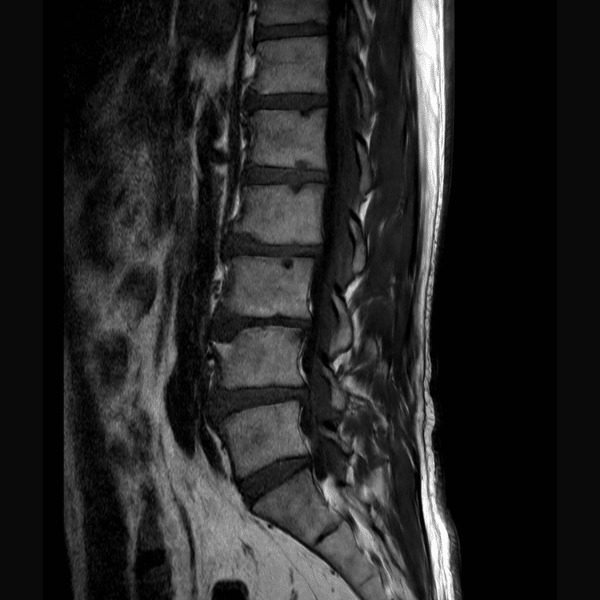

L-Spine T1WI

3.0T Philips Ingenia CX

2D TSE

(L) 0.4×0.9×3.0 mm

(R) 0.5×1.1×3.0 mm

Conventional SwiftMR™ 03:53 00:34 (85% Faster)